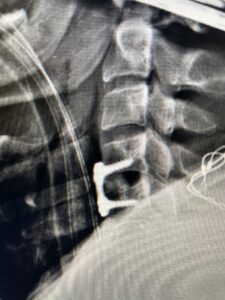

This 47-year-old male who four months prior was lifting weights developed sharp pain in his neck. After that he developed progressive numbness in his arms, neck pain and headache. He said that the right arm was worse than the left. On examination the patient had long tract weakness on the right side which included his triceps, finger extensors, hip flexors, and dorsiflexors. The patient did not have hyperreflexia. MRI (Fig. 2) demonstrated a massive, extruded disc herniation with severe cord compression. The patient because of progressive myelopathy and spinal cord compression was indicated for anterior cervical discectomy and fusion at C4-5 (Fig. 3). Patient had significant improvement of weakness and numbness post operatively.

Fig. 3 Intraoperative lateral cervical X-Ray demonstrating C4-5 ACDF